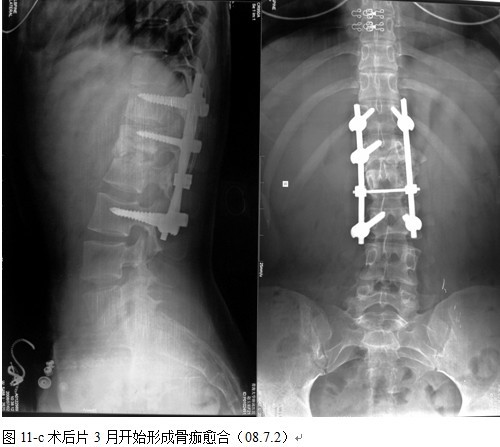

本组手术用时间3~4h , 平均3.5h 。术中出血300~500ml , 平均约350ml 。术后症状完全缓解,无神经功能障碍加重等并发症,1例营养差的老年患者伤口出现窦道,1例因肝功能差,术后未口服抗痨药,伤口出现窦道,经换药后二期愈合,其余病例伤口均一期愈合。马尾神经受损的患者术后基本恢复正常。术后一周后凸角平均 5.4°后凸畸形平均矫正90%以上, 最终后凸角平均8.3°,后凸角度平均丢失4.2°。随访3个月有87%(40/46)有骨痂形成,6个月91.3%(42/46)明显骨性愈合(见图),其余4例9-12个月内愈合,随访时间3-32个月,平均11个月,46例患者中2例在术后2个月和3个月时背部形成脓肿,换药后治愈。2例出院1月后并发结核性脑膜炎,治疗后好转。1例因椎弓根钉偏外,刺激神经根,5个月后从侧方脱出,疼痛加重,因前后路植骨完全愈合,取出后症状完全缓解。